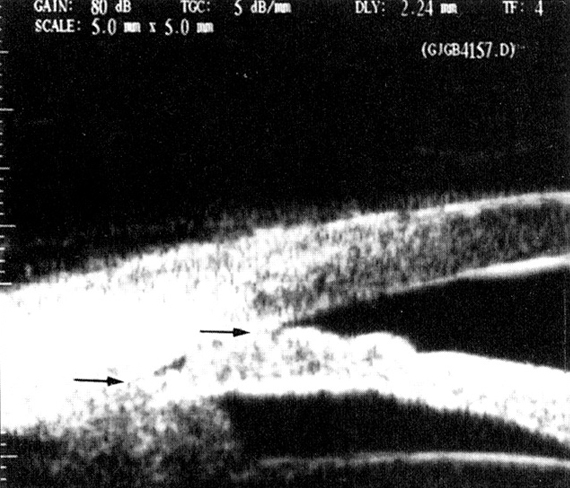

Steam cells o celulas madres se aplican al tratamiento de enfermedades corneales, glaucomas, enfermedades pigmentatias y degeneracion macular.